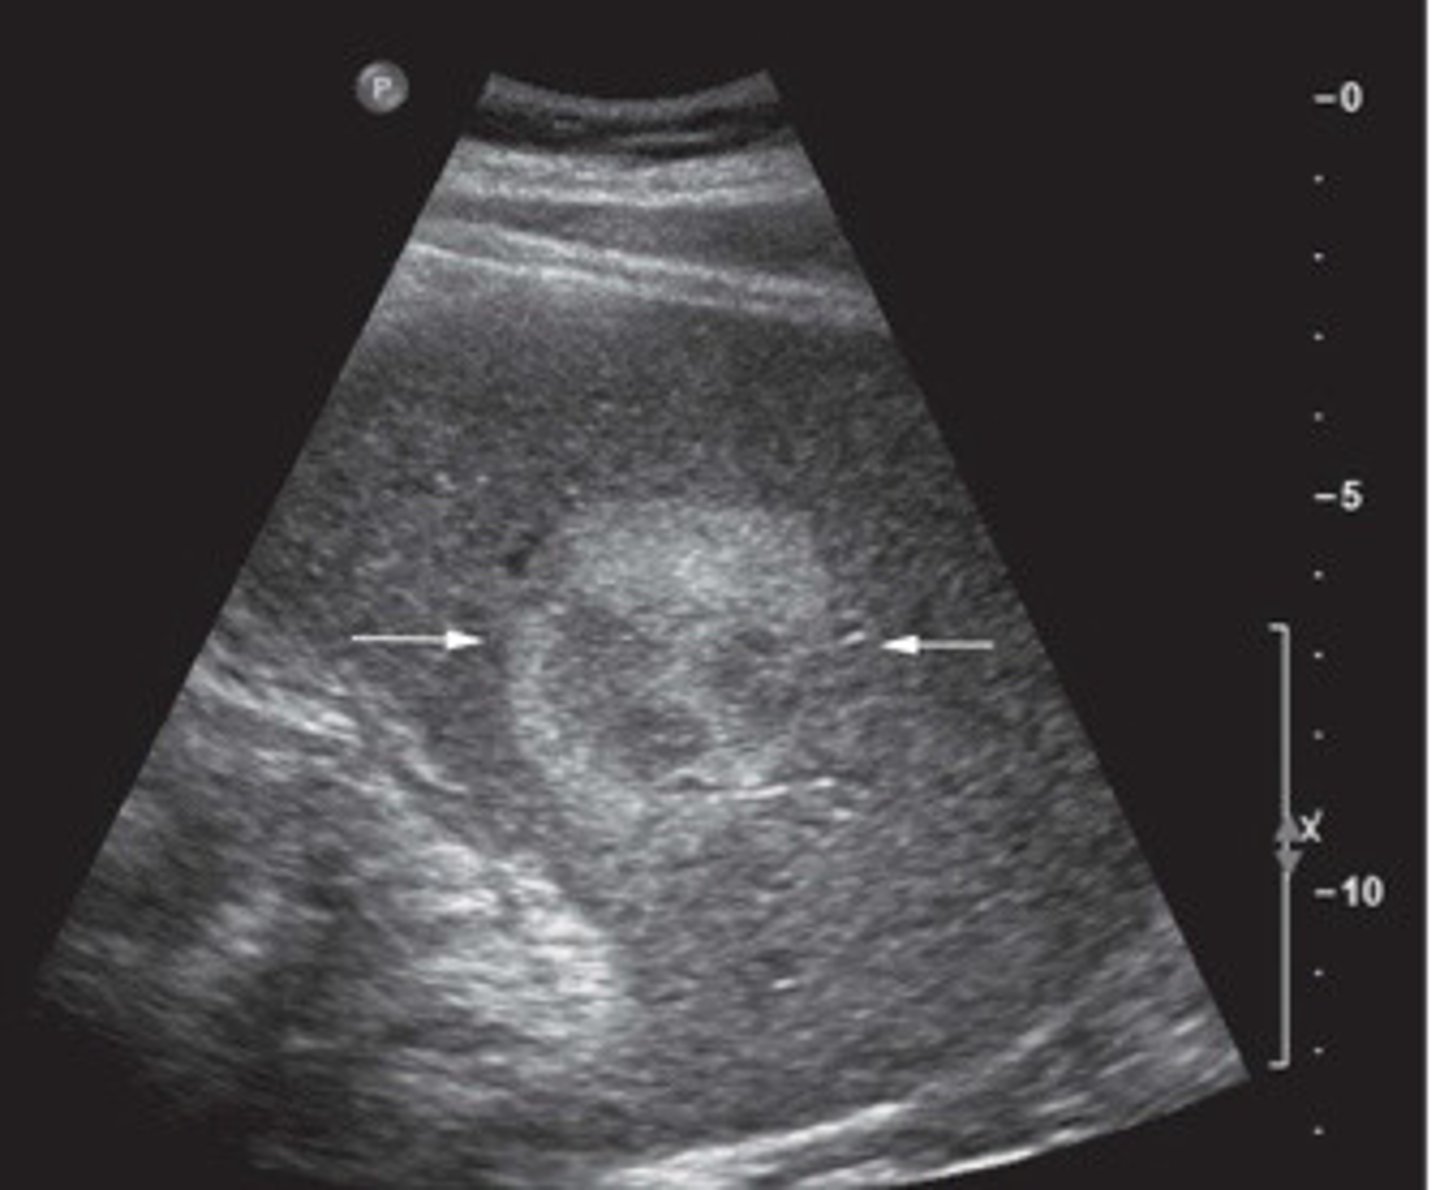

What does this image show

Atypical appearance of hemangioma